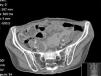

In the third month after transplantation, she complained of diffuse abdominal pain, with normal intestinal transit. Aerocolia in the terminal ileum and a slight thickening of the wall of the ascending colon were identified on abdominal ultrasound. Distal Intestinal Obstruction Syndrome (DIOS) was assumed, pro-kinetics drugs, oral rehydration and osmotic laxatives were prescribed and she was discharged. Forty-eight hours later, she was hospitalised due to non-resolving complaints (crampy diffuse abdominal pain). On day 2, during physical examination, an abdominal mass was identified in the right inferior abdominal quadrant. She was submitted to an abdominal computed tomography (CT) scan showing thickening of the wall of the ascendant colon and abnormal contrast accumulation, raising suspicion of an anterior intestinal wall perforation, despite no evidence of free air/fluid collection in the abdominal cavity (Fig. 1). A right hemicolectomy and reconstruction were performed without complications. The anatomopathological examination of the intestinal tissue showed necrotic areas and the presence of wall and vascular invasion by fungal hyphae, with distinction between Mucor or Aspergillus impossible on observation (Fig. 2a and b). The patient started empiric antifungal therapy with amphotericin, and switched to voriconazole after a positive test of polymerase chain reaction for Aspergillus.